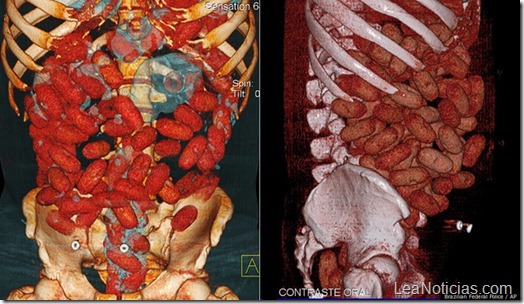

Ingerir cápsulas o bolsas con cocaína es una práctica recurrente entre traficantes. sin embargo, las autoridades cuentan con tecnologías que permiten escanear el interior del estómago en busca de drogas. ¿Cómo se ve el interior de una persona con una buena dosis de cocaína en sus entrañas?

En el interior del estomago de este joven, la policía detectó 72 pequeñas bolsas repletas de cocaína, que previamente había ingerido. Posteriormente el joven, quien ha sido identificado únicamente como F.B.B, fue trasladado a un hospital en donde le fue extraído el cargamento. Se comprobó que llevaba alrededor de 2 onzas de cocaína (poco más de cincuenta gramos) y ahora enfrenta cargos por tráfico de drogas internacional, lo cual podría acarrearle hasta 15 años de prisión.

Pero más allá del delito —que es una práctica cotidiana en decenas de aeropuertos alrededor del mundo— lo interesante es que se publicaron imágenes de su estómago repleto de pequeñas envolturas, algo que raramente sucede.